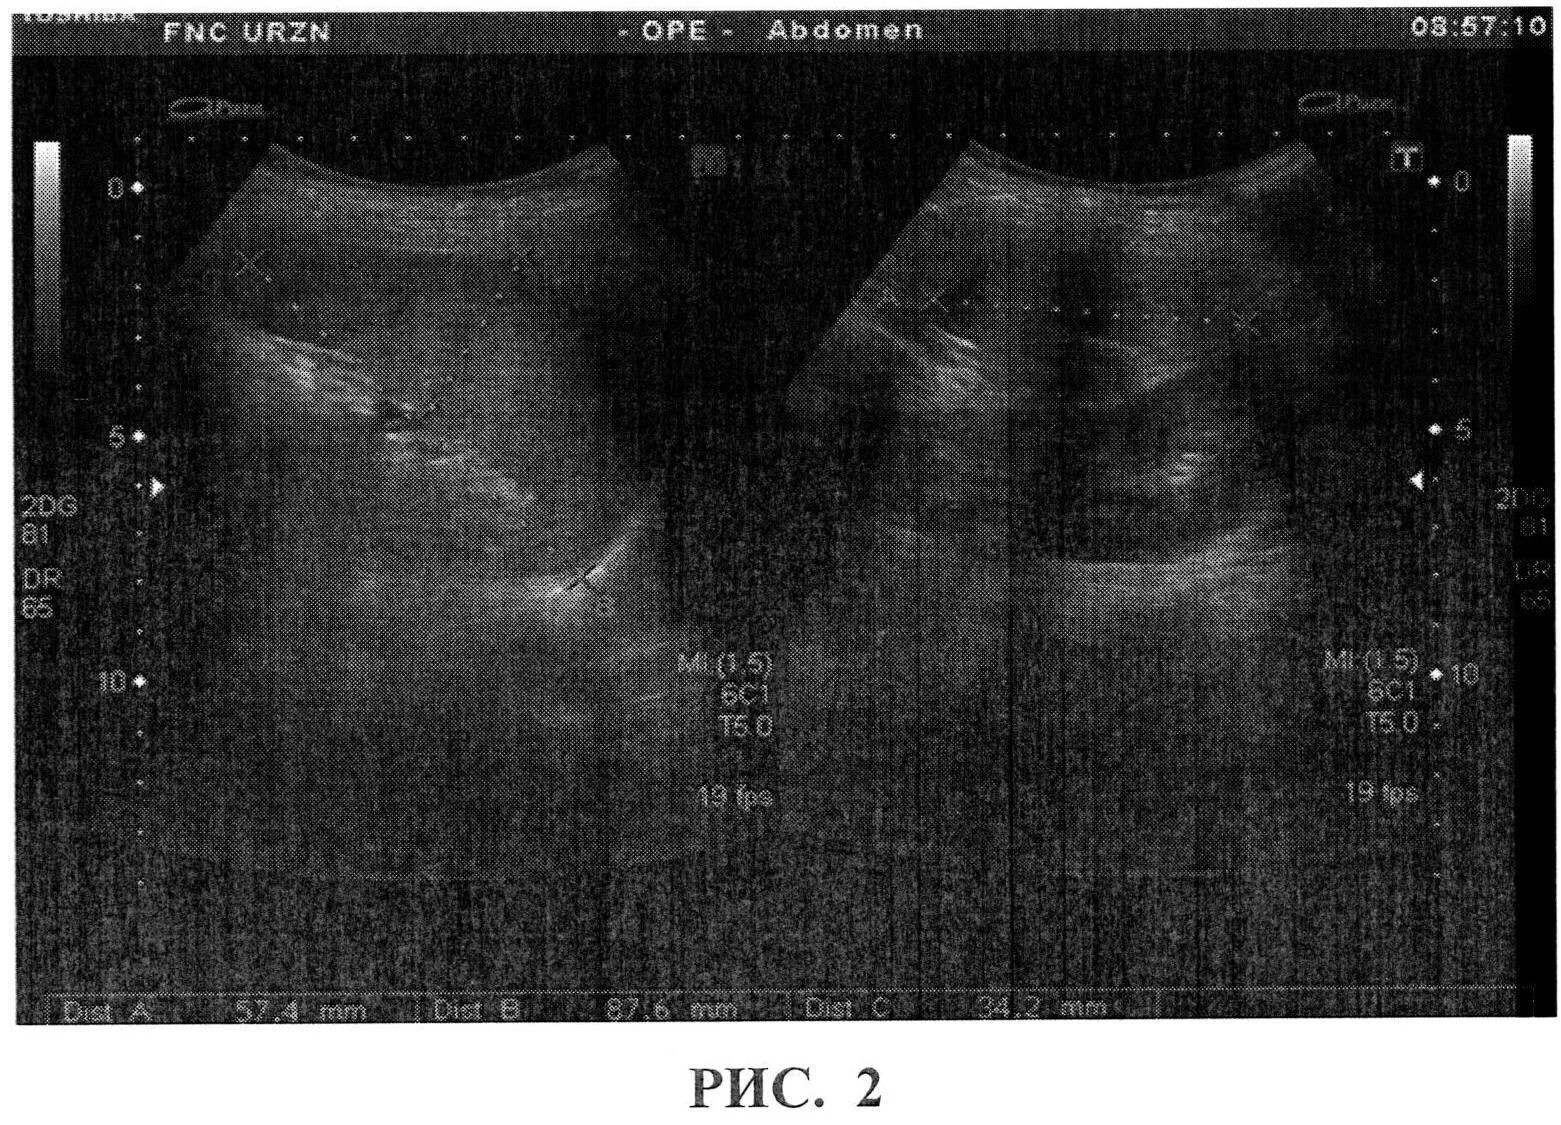

Селезенка размеры норма у взрослых